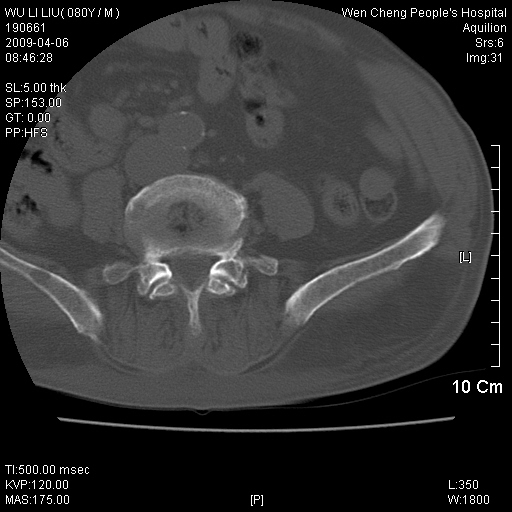

以下是引用zjzjr在2009-4-7 12:13:00的发言:[br]支持多发性转移瘤,右股骨颈骨折,腰椎亦有压缩性骨折.肝内胆管结石伴胆内外胆管扩张,左肾结石.

以下是引用liaoqiang在2009-4-7 8:44:00的发言:[br]考虑多发性骨髓瘤伴肝肺转移、肝内胆管结石、左肾结石、右股骨颈骨折。

以下是引用余辉在2009-4-7 8:52:00的发言:[br]椎骨及骨盆骨质疏松,骨破坏主要累及椎体,各骨破坏较广泛,各病灶边缘均较清晰锐利,血沉增快,白细胞增高.支持考虑多发骨髓瘤,建议查本尿周氏蛋白.[br]胆内胆管及左肾结石[br]右股骨颈骨折,考虑病理性